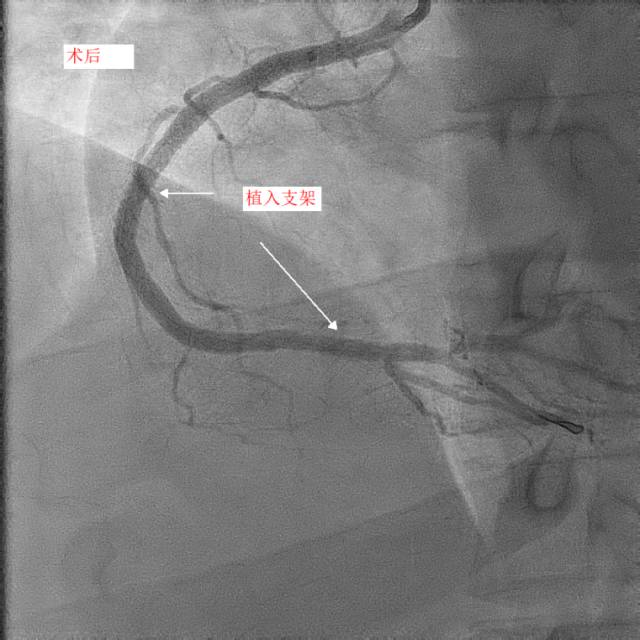

第二天,小天和父亲同一天接受冠脉造影和手术治疗,冠脉造影进一步明确了:小天冠状动脉回旋支完全堵死、前降支90%堵塞,而右冠状动脉也仅有一丝血流通过。造影中医生发现,小天的血管狭窄已经有一段时间,其中的右冠状动脉已经产生了侧支循环。随后医生在患者右冠状动脉里放入了两个支架,恢复了血流。

两天后,医生再次手术解决了左前降支的问题,至于回旋支因为先天血管发育较小,可暂时观察,后续再处理。